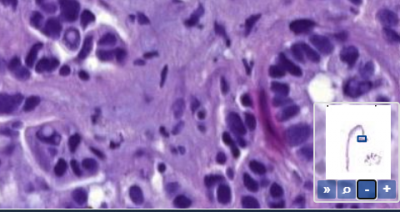

ที่มุมล่างขวาของวิวพอร์ต คุณจะเห็นภาพขนาดย่อของสไลด์ของคุณ โอเวอร์เลย์สีแดงจะระบุว่าส่วนใดของสไลด์ที่ถูกแสดงอยู่ในวิวพอร์ตในปัจจุบัน

คุณสามารถเพิ่มหรือลดภาพรวมด้วยปุ่มต่างๆที่อยู่ใต้ตัวควบคุม

โดยคุณยังสามารถเปิดใช้งานการติดตามได้ หมายความว่าพื้นที่ที่คุณดูไปแล้วบนสไลด์จะถูกแสดงเป็นสีอ่อนกว่าพื้นที่อื่น